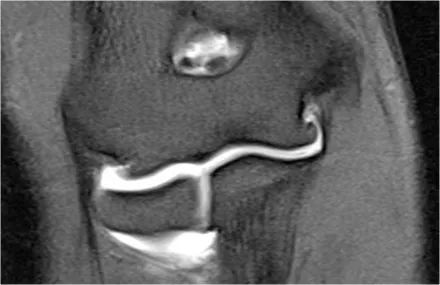

通过将隧道放置在内侧上髁中来完成UCL修复。它们对耸高的结节进行了操作,并在它们之间放置了移植物。

这张射线照片是一名26岁的职业棒球运动员,他曾进行过UCL重建。注意隧道(箭头)。这种操作通常很有效。

MR图像,您可以看到内侧上髁的隧道。

在尽管高低不平的冠状图像几乎看起来像一个正常的UCL。

下面的图像,我们看到修复后患者表现不佳的图像-骨的碎裂和移植物的破坏。在CT扫描中,更好地理解通过隧道存在裂缝。